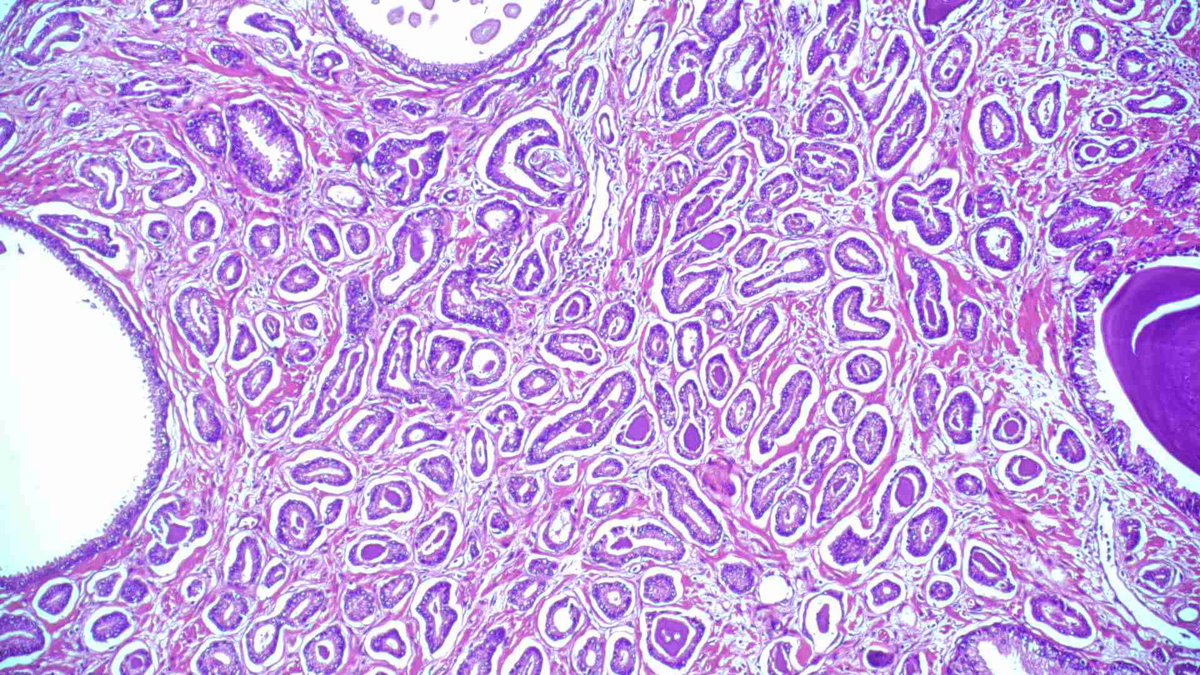

#GUpath TURBT: non-inv papillary urothelial carcinoma (PUC) with admixed microcysts I don't consider this "glandular differentiation" -- I hold out for true apical cytoplasm/cribriform/villoglandular forms/lumina to call pTa PUC w/glandular diff